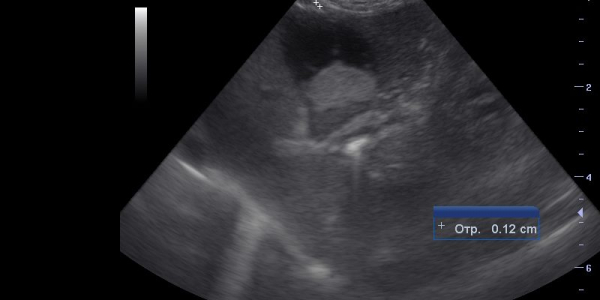

УЗИ желчного пузыря и печени выполняется с использованием специального ультразвукового аппарата. Во время процедуры пациенту необходимо лечь на спину, а врач наносит на кожу специальный гель, чтобы обеспечить контакт с датчиком аппарата. Затем аппарат передвигается по коже, излучая ультразвуковые волны и принимая их отражения от органов. Эти отраженные волны обрабатываются компьютером и отображаются на экране в виде черно-белых изображений.

Диагностические показатели УЗИ

Размеры желчного пузыря и печени могут варьироваться у разных людей, но при нормальном состоянии этих органов они имеют определенные пределы. Обычно размеры желчного пузыря в норме не превышают 4-5 см в длину и около 3 см в ширину. Размеры печени также зависят от индивидуальных особенностей, но в среднем обычно не превышают 15 см в вертикальном направлении и 20-25 см в горизонтальном.

Кроме размеров, врач при УЗИ обращает внимание на структуру органов. Нормальная структура желчного пузыря характеризуется однородностью, ясными контурами и отсутствием опухолей или камней. Печень также должна иметь однородную структуру, без присутствия фокусов патологии.